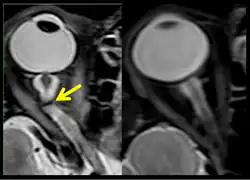

Figure 10: MRI (R+30 days) of the fourth case of visual changes from long-duration spaceflight. There is prominence of central T2-hyperintensity of the optic nerves bilaterally, right greater than left approximately 10 to 12 mm posterior to the globe (arrow) that represents an element of optic nerve congestion.

Figure 11: MRI (R+30 days) of the fourth case of visual changes from long-duration spaceflight. Tortuous optic nerve and kink on left (arrow). Control orbit on the right.